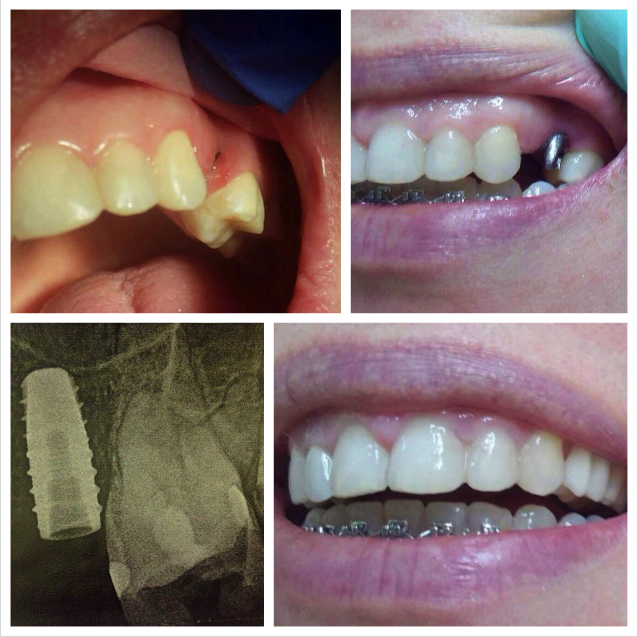

Dental implants are small, highly developed screws made out of pure surgical titanium. The implats are being placed (often by screwing) into the jawbone in order to replace missing teeth. A temporary crown (usually plastic) covers the gap until the implant healed into the bone.

After the healing period that can take between 3 months for the lower jaw up to 6 months for the upper jaw in wich the implant is firmly attaching to the jawbone, the permanently crown now can be attached to the implant.

Implants can be used to replace one or more missing teeth in the front as well for rear teeth. Also they can be used to support bridges or removable dentures in case of more missing teeth.